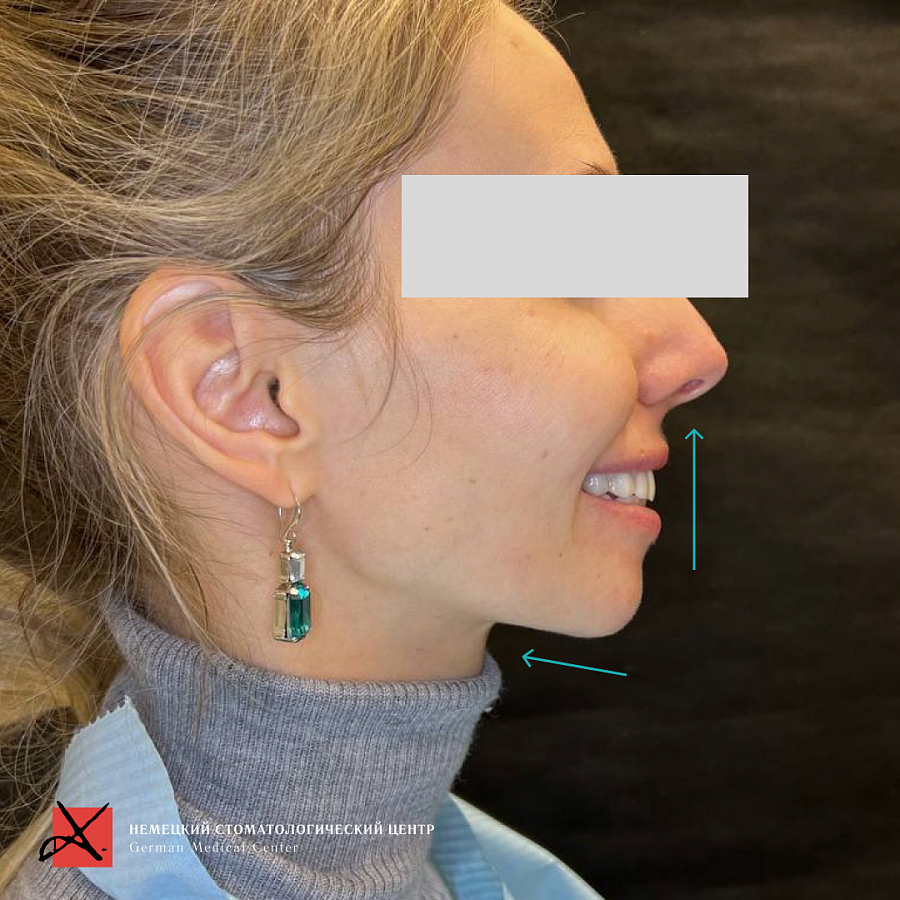

В результате мы получили изменение контура лица, улучшение мимики мускулатуры лица, далее мы улучшили состояние сустава (он вообще перестал беспокоить!), шея расслабилась, благодаря чему ушли головные боли и боли от напряжения.

Также лечение привело к существенному изменениям внешнего вида пациентки.

В результате мы получили изменение контура лица, улучшение мимики мускулатуры лица, далее мы улучшили состояние сустава (он вообще перестал беспокоить!), шея расслабилась, благодаря чему ушли головные боли и боли от напряжения.

Также лечение привело к существенному изменениям внешнего вида пациентки.